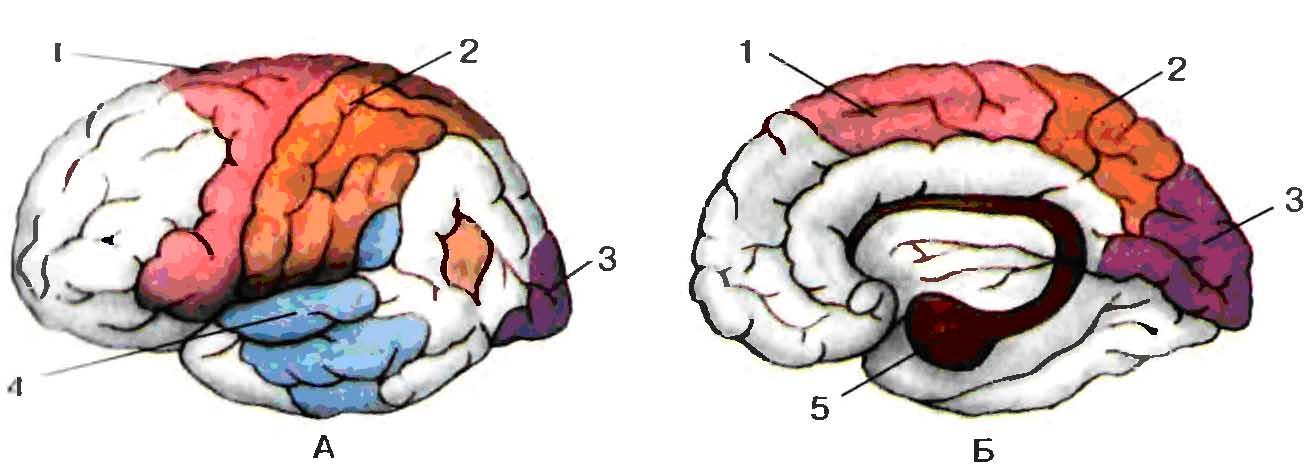

Схема чувствительных зон новой коры мозга